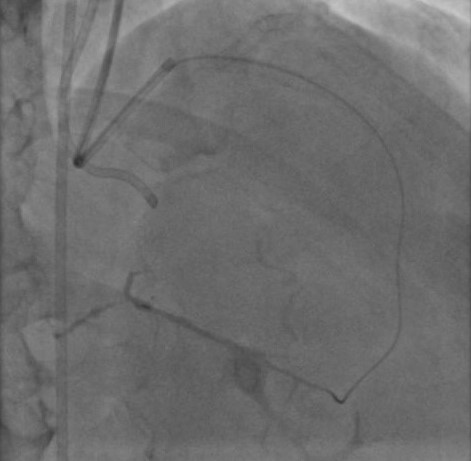

G.H.M.S.S., 46 anos, com hipertensão, diabetes, dislipidemia, história familiar de doença arterial coronariana (DAC) precoce e ex-tabagista. Foi internado em novembro de 2021 e diagnosticado com acidente vascular cerebral (AVC). Durante o internamento, realizou ecocardiograma para investigar possíveis causas do AVC, que evidenciou fração de ejeção de 46% com hipocontratilidade do ventrículo esquerdo mais acentuada em parede inferior. Na ocasião, tinha desconforto retroesternal em aperto e dispneia aos esforços. A angiotomografia demonstrou DAC multiarterial e ao realizar cateterismo foi visto: descendente anterior (DA) com lesão moderada no óstio e duas lesões graves (90%) no 1/3 proximal; circunflexa (Cx) com lesão grave no 1/3 proximal e no 1/3 médio; 1º marginal (Mg) com lesão grave no óstio; coronária direita (CD) dominante ocluída no 1/3 proximal; circulação colateral da coronária esquerda para a descendente posterior grau III. Foi indicado cirurgia de revascularização miocárdica, porém o paciente recusou e insistiu para realizar o procedimento via percutânea. Dessa forma, realizou angioplastia transluminal coronária em 02/22 que tratou as lesões em DA, Cx e 1º Mg e foi optado por tratar a oclusão crônica em CD posteriormente.Em julho, foi feito o procedimento com a tentativa de acessar retrogradamente o 1/3 distal da coronária direita com a corda guia Samurai e posteriormente com a corda guia 0,014 Pilot 150 com o suporte do microcateter Mamba sem sucesso, com dissecção da capa distal da oclusão. Então, houve tentativa de cruzar por via anterógrada com a guia Fighter, também sem sucesso. Terceira tentativa de puncionar a capa proximal da oclusão com a guia Hornet 10 também falhou, porque a guia não seguiu a curvatura da CD e pareceu seguir pela luz de um marginal direito. Por último, foi optado por utilizar um novo microcateter Mamba e realizar uma dissecção proximal da CD com um balão e seguir com a guia Pilot 150 e o microcateter através do espaço sub-intimal até o 1/3 distal da CD, realizando dilatação do espaço com balão. Guiado por ultrassom intra-coronário, foi feito o implante de stents em todo o segmento da CD no espaço sub-intimal e realizados, ainda, pós dilatação intra-stent. Ao final do procedimento, o ultrassom demonstrou boa expansão, porém com poucas áreas de má aposição, sendo optado por não realizar nova pós-dilatação, uma vez que havia ruptura do vaso com dilatação agressiva no espaço sub-intimal. Após o procedimento, o paciente evoluiu estável e assintomático, recebendo alta hospitalar depois de 3 dias com AAS e Ticagrelor.